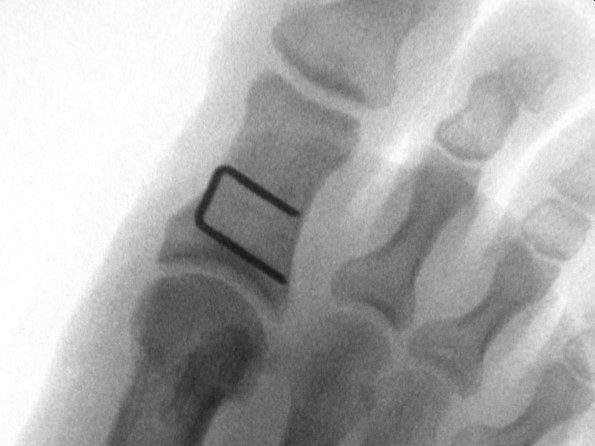

Über einen kleinen Hautschnitt auf der Innenseite des Grundglieds der Großzehe wird ein keilförmiges Knochenstück entnommen. Der Knochen wird dann in die korrigierte Stellung gebracht und mit einer Titan-Klammer (Staple) stabil fixiert. Die Klammer verbleibt dauerhaft im Körper – eine Entfernung ist in der Regel nicht notwendig.

Wir bevorzugen in den meisten Fällen die mini-open Technik. Sie ermöglicht eine direkte Sicht auf den Knochen und damit eine präzise Dosierung der Korrektur – das heißt, wir können genau bestimmen, wie viel Knochengewebe entnommen wird. Das ist entscheidend für das Ergebnis. Eine retrospektive Vergleichsstudie mit 210 Füßen zeigte, dass bei der minimalinvasiven Variante in über 50 Prozent der Fälle die laterale Gegenkortikalis versehentlich perforiert wurde – bei der offenen Technik waren es nur 14 Prozent. Zudem war die knöcherne Konsolidierung bei der offenen Methode nach 6 Wochen abgeschlossen, bei der minimalinvasiven erst nach 12 Wochen (Schilde S. et al., Foot Ankle Int, 2021).

Welches Implantat wird bei der Akin Osteotomie verwendet?

In der Regel verwenden wir eine Titan-Klammer (Staple), die den korrigierten Knochen stabil fixiert. Bei der minimalinvasiven Variante kommt stattdessen eine Schraube zum Einsatz. Welches Implantat sinnvoll ist, hängt von der gewählten Operationstechnik ab.